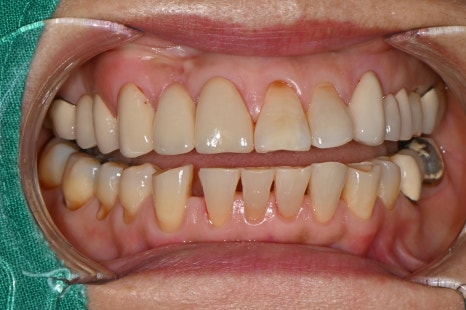

처음 내원 하셨을때 구강 내 사진

➤초진 진단 소견

앞니 심미 보철과 어금니 임플란트 치료를 계획하기 전, 환자분의 초기 상태를 확인한 모습입니다.

치아 배열, 상실 부위, 기존 보철 상태 등을 종합적으로 진단한 결과, 다음과 같은 치료 계획을 안내드렸습니다:

오른쪽 아래 어금니 부위(#45~47): 오래된 브릿지를 제거하고 #45 47 크라운 새로 제작하는 것을 권장드렸으며, #46 빈자리는 기존 브릿지 대신 임플란트 1개 식립을 안내드렸습니다.

앞니 부위(#11): 치경부 마모가 심하여 추가적인 보철 치료가 필요한 상태였습니다.

아래 앞니 부위(#43, #42): 치아 사이의 공간이 커져 크라운을 이용한 심미적 개선을 계획했습니다.